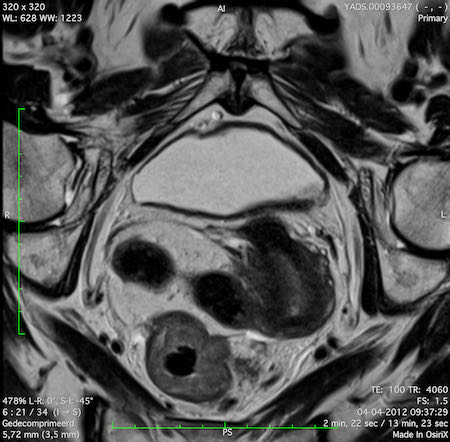

Hình ảnh

Các hình ảnh được cung cấp cho thấy ung thư biểu mô tế bào nhẫn với tình trạng dày lan tỏa thành trực tràng, hình ảnh bia bắn điển hình, và sự xâm lấn mỡ mạc treo trực tràng.